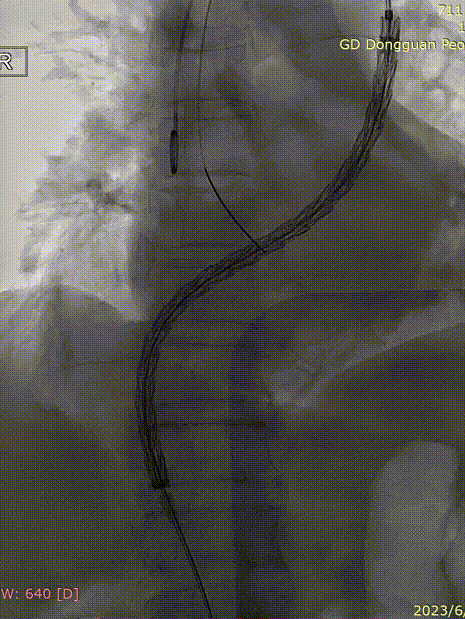

3. 交换导丝为Lunderquist,置入GORE® DrySeal 亲水涂层导引鞘,因内膜较差,为防止导丝从假腔中穿过,引入90cm长鞘,逐步造影,确认导丝全程位于真腔。

gore医疗怎么样「胸有乾坤」危如累卵 妙手回春——Conformable GORE®TAG®胸主动脉覆膜支架应用于高龄急性主动脉夹层治疗_https://www.jmylbn.com_新闻资讯_第24张

gore医疗怎么样「胸有乾坤」危如累卵 妙手回春——Conformable GORE®TAG®胸主动脉覆膜支架应用于高龄急性主动脉夹层治疗_https://www.jmylbn.com_新闻资讯_第25张

gore医疗怎么样「胸有乾坤」危如累卵 妙手回春——Conformable GORE®TAG®胸主动脉覆膜支架应用于高龄急性主动脉夹层治疗_https://www.jmylbn.com_新闻资讯_第26张